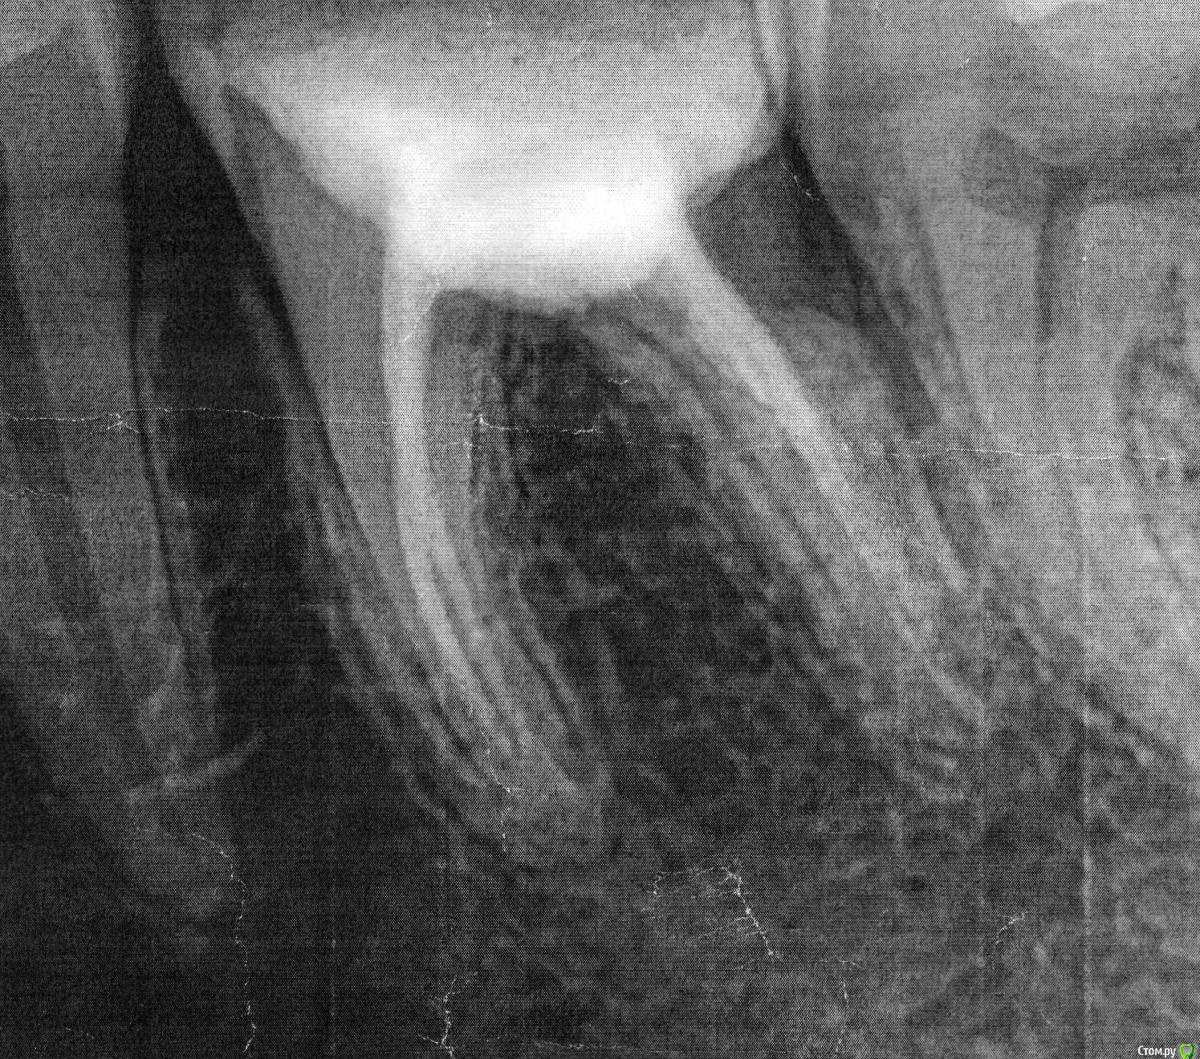

Ангеланя Опубликовано 12 февраля, 2015 Поделиться Опубликовано 12 февраля, 2015 Здравствуйте! Помогите пожалуйста, я не знаю что делать, мне очень нужен совет.Проблема с зубом 3.6 возникла еще в 2004 году, он у меня разрушился (во время беременности), лечили очень долго - закладывали мышьяк, удаляли нервы, поставили обычную пломбу, с которой я проходила 8 лет! Пломба выпала в 2012. Я заменила ее на световую, не помню точно, но каналы вроде тоже перепломбировывали. Прикрепляю снимок, сделанный через пол года после перепломбировки. Зуб меня не беспокоил, ходила я с новой пломбой 2 года. Но недавно откололся кусочек и мне острый край создавал дискомфорт, пошла к стоматологу.Пошла в частную клинику, работающую по ОМС.Значит пломбу она вскрыла, стала тыкать - мне больно, поставила 3 или 4 укола, говорит, что стал виден у соседнего зуба поверхностный кариес, лечила вроде как его, световую пломбу накладывала. Я не знаю что конкретно она делала. В завершении она наложила мне временную пломбу, и сказала, что этот зуб идет под коронку, смысла его вновь пломбировать нет, я с ней согласилась, мне до нее уже об этом говорили. На следующий день прихожу к ортопеду, он отправил на снимок, посмотрев его, сказал,что нужно перелечивать канал, к тому же он видит воспалительный процесс. Прихожу я к терапевту, уже к другому, в другую клинику, платную. Она посмотрела мои снимки и просто ошарашила меня - зуб подлежит удалению!!!!!! Отсутствует бифуркация, следовательно будет воспалительный процесс периодонта. Коронка противопоказана, и постоянная пломба тоже, т.к. через несколько месяцев зуб разрушится окончательно. Она позвала ортопеда (другого), та подтвердила ее мнение, и высказала недоумение, почему ортопед, который меня смотрел до этого не заметил.В-общем я в пребываю в шоке. Зуб терять не хочу. Посоветуйте пожалуйста,что можно сделать в этой ситуации, для меня очень важно сохранить этот зуб. Я подозреваю, это врач при вытаскивании пломбы повредила зуб. Сравните снимки - мои подозрения подтверждаются? Я хочу поехать в ту клинику и написать претензию, ведь из-за ее неосторожных действий я потеряю зуб. Что мне можно потребовать, может компенсацию? Посоветуйте, а стоит ли вообще разбираться, ведь зуб не вернешь. Или все-таки можно хоть что-то сделать? Так хочется, чтоб доктор у которой я сегодня была ошибалась! еще раз напомню, на первом фото - снимок 2012 года, на втором - сегодняшний день с временной пломбой. Ссылка на комментарий

shishok Опубликовано 12 февраля, 2015 Поделиться Опубликовано 12 февраля, 2015 Возможно и нет перфорации(угол съёмки другой).КТ в помощь.Но мне не нравится разрушение задней стенки ниже уровня десны.ИМХО. Ссылка на комментарий

Ангеланя Опубликовано 12 февраля, 2015 Автор Поделиться Опубликовано 12 февраля, 2015 Возможно и нет перфорации(угол съёмки другой).КТ в помощь.Но мне не нравится разрушение задней стенки ниже уровня десны.ИМХО.у меня есть еще один снимок, сделанный сегодня., а снимок выше - от 9 числа, когда первый раз пошла к ортопеду Ссылка на комментарий

Гарриевич Опубликовано 12 февраля, 2015 Поделиться Опубликовано 12 февраля, 2015 Для начала прекратите сыпать обвинениями на всех подряд. Первый снимок сделан в прямой проекции, а второй под углом сверху, отсюда и разница. На последнем снимке вообще ничего не видно, он не информативен. Хотите разобраться и быть уверенной идите к хорошему доктору, тут на форуме есть несколько докторов с Вашего города 1 Ссылка на комментарий